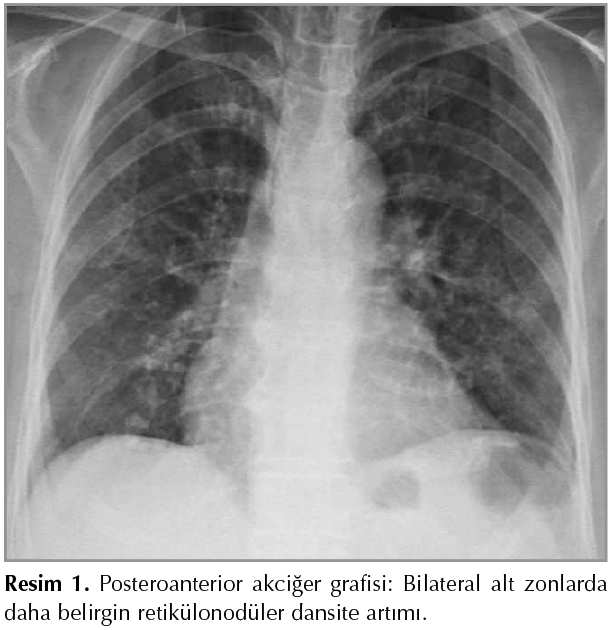

Yetmiş ?? yaşında kadın hasta, ?? haftadır devam eden ?ks?r?k yakınmasıyla polikliniğimize başvurdu. ?z ge?mişinde bir ay ?nce dış merkezde endometriyum adenokarsinomu tanısı mevcuttu. Solunum sistemi bakısı olağan olup vital bulgular ve diğer sistem bakıları da normaldi. Laboratuvar bulgularında hemogram, rutin biyokimya testleri ve CRP normal sınırlarda bulundu. Akciğer grafisinde alt zonlarda daha belirgin retik?lonod?ler dansite artımı mevcuttu (Resim 1). Bu nedenle ?ekilen toraks bilgisayarlı tomografi (BT)'de parankim penceresinde bilateral kaviter lezyonlar izlendi (Resim 2). Fiberoptik bronkoskopide (FOB) endobronşiyal lezyon saptanmadı. FOB ile sağ orta lobtan bronkoalveoler lavaj (BAL) ve fır?a yapıldı. Bronş aspirasyonunda bakteriyel ve mantar k?lt?rlerinde ?reme olmadı, asidorezistan basil (ARB) direkt bakıları negatif sonu?landı. BAL ve fır?a sitolojileri benign olup BAL'da spesifik bulgu saptanmadı. Bakılan ANA, p-ANCA, c-ANCA romatolojik markerları negatif sonu?landı. Tanısal ama?lı BT eşliğinde transtorasik ince iğne aspirasyon biyopsisi (TTİİAB) yapıldı. Hastanın patoloji sonucu "Malign sitoloji; h?cre bloğunda izlenen iğsi n?kleuslu atipik h?crelerde, imm?nhistokimya (İHK) ile pansitokeratin, ?strojen resept?r? (ER), progesteron resept?r? (PR) pozitif; vimentin negatif saptanmıştır. Klinik ?yk? eşliğinde bulgular; endometriyum adenokarsinom metastazı ile uyumludur" olarak raporlandı (Resim 4). Hasta Jinekolojik Onkoloji B?l?m?ne y?nlendirildi. Endometriyum karsinomu ve akciğer metastazı tanıları olan hastaya kemoterapi ?nerildi. Ancak hasta ve yakınları kemoterapiyi kabul etmedikleri i?in semptomatik tedaviyle takip edildi. Olgumuzda tanıdan itibaren 2 yıl ge?miş olup performansı iyi, ?ks?r?k ve bel ağrısı yakınması mevcuttur.

Resim 1